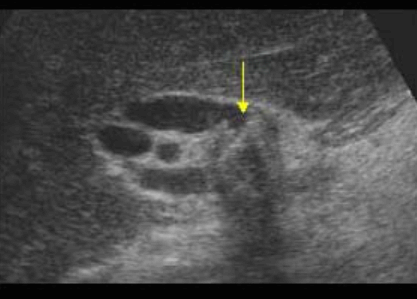

US finding

- 간내담관은 확장되고 간외담관은 정상이다.

- 담낭은 위축되며, 간외담관은 담즙 흐름이 없는 담관으로 묘출된다.

- 폐쇄된 담관부위에 종양의 윤곽이 보일 수 있으나 초음파상 발견하기 어렵다.